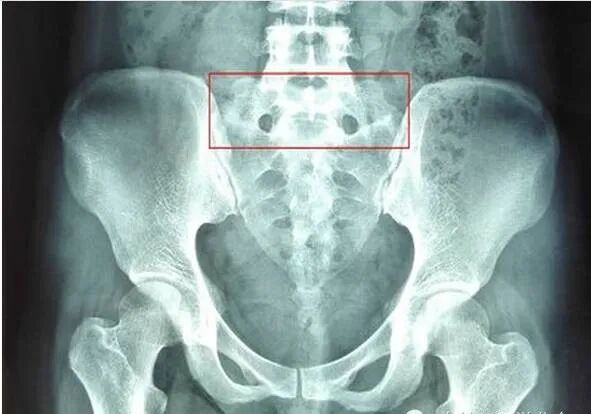

第五腰椎横突肥大(L5腰椎横突肥大)是指第五腰椎横突发育异常, 一般临床无症状,但随着年龄的增长、劳损或外伤等,均可出现腰腿痛, 也是导致患者发生慢性腰腿痛的原因之一

对L5腰椎横突肥大引起下腰痛的原因进行分析认为,L5腰椎横突粗 壮且轻度上翘,与髂骨基本平行,但有一定间隙。L4、5脊神经联合支下 行经过L5横突前方,当L5横突出现肥大,可直接向下压迫L5神经,对 其可产生压迫,加之患者腰部活动,可引起坐骨神经压迫症状;L5 腰椎 横突处为肌肉、韧带附着点,最易引发损伤,而横突越大,越易引发附着 点损伤,引起局部无菌性炎症,产生胺类、缓激肽及乳酸等代谢产物,并 在局部蓄积引起腰痛。这些代谢物可使其附近毛细血管扩张,通透性加强, 局部组织充血、水肿,引起纤维蛋白渗出增加,出现粘连,如无进一步治 疗,可引起横突更为肥大,导致患者症状再次加重;L5 腰椎横突肥大与 骶髂骨接触或假关节形成,腰椎呈骶化趋势或骶化不全,可能使这种机会 增加,当肥大横突与骶骼骨接触时,由于二者间间隙较小或无间隙,活动 或暴力损伤均可能引起周围软组织及骨膜发生损伤,引起下腰部痛。另外, L5 腰椎横突肥大与骶股长骨形成假关节时,由于关节软骨较薄或缺如, 关节面高低不平,间隙狭窄,形成损伤性关节炎;随着时间的延长,年龄 的增长,关节面增生硬化,出现骨唇,软组织充血水肿,使挤压的神经末 梢产生疼痛,甚至可引起相信椎间孔变窄,刺激L5 神经根,引起下肢放 射性疼痛,或麻木。

总之,L5 腰椎横突肥大,多发于青壮年、体力劳动者,由于肥大的 横突或形成的假关节压迫L5 神经、损伤附着点等原因,,是导致患者慢 性腰腿痛的原因之一,在诊断上可结合患者的临床症状及X 线片等检查 进行确诊,并对症给予治疗,解除患者痛苦。